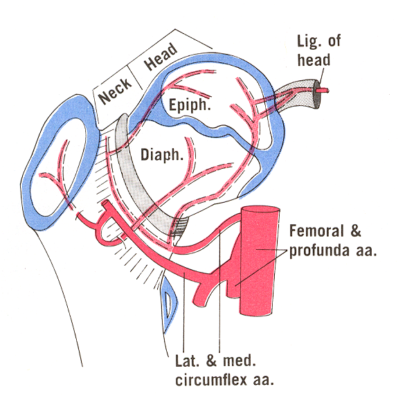

Phần lớn lượng máu cung cấp cho chỏm xương đùi đến từ các nhánh mũ trong và ngoài của động mạch đùi sâu, là một nhánh của động mạch đùi (động mạch đùi sâu là nhánh xuyên sâu ở vùng đùi trên). Các động mạch mũ đùi trong và ngoài nối với nhau để tạo thành một vòng mạch quanh cổ xương đùi, từ đó nhiều động mạch nhỏ phân nhánh để tưới máu cho chỏm xương đùi. Một nguồn cung cấp máu trực tiếp khác là từ động mạch của dây chằng tròn. Dây chằng tròn là dây chằng nối chỏm xương đùi với ổ cối. Động mạch dây chằng tròn đi bên trong dây chằng này, sự đóng góp nuôi dưỡng của động mạch này chỉ có ý nghĩa ở trẻ em.

Có hai đường nối thông quan trọng cung cấp lưu lượng máu phụ (mặc dù hạn chế) để hỗ trợ chỏm xương đùi. Một là thông nối hình chữ thập (cruciate anastomosis), giữa động mạch mông dưới và động mạch mũ đùi trong. Hai là thông nối mấu chuyển, giữa động mạch mông trên và động mạch mũ đùi trong/ngoài. Cả động mạch mông trên và mông dưới đều là nhánh của động mạch chậu trong (còn được gọi là động mạch hạ vị), là động mạch chính của khung chậu và cung cấp máu cho một phần của mông và đùi sau.

Chỏm xương đùi khớp nối với ổ cối. Nguồn cung cấp máu cho ổ cối chủ yếu đến từ nhánh ổ cối của động mạch bịt, cùng với góp phần từ các nhánh mu của động mạch bịt và các nhánh sâu của động mạch mông trên.

Do tuần hoàn bàng hệ bị hạn chế, nếu cấp máu cho chỏm xương đùi bị gián đoạn có thể dẫn đến thiếu máu cục bộ. Nếu nguồn cung cấp máu không phục hồi kịp thời, điều này sẽ dẫn đến cái chết dần dần của các tế bào xương, hoại tử, sau đó là xẹp bề mặt khớp và cuối cùng là thoái hóa khớp.